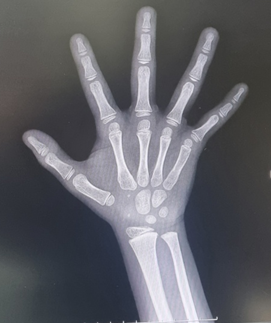

골연령이 몇세 정도 인가요?????

이정도면 골연령이 만으로 몇세정도 인가요?

사진상으로는 정확한 상태를 확인하기는 어려우며 손가락과 손목뼈의 발달 정도와 성장판을 보면 완전하지 않을 수 있고 어디까지나 추측으로 보았을때 10대 후반정도로 보이며 정확한 상태는 병원에 방문하시어 검사 및 상담 가져보시면 좋을 것으로 생각됩니다.

사진상으로 많은걸확인할수는없지만 손가락과 손목뼈의 발달정도와 성장판을보면 완전하지않기때문에 10대후반정도로 보입니다 하지만 실제나이나 성별또는 성장환경에따라서 달라질수있기때문에 본인의 골연령을 확인하기위해서는 병원에서 전문의와상담을받아보는것이 필요할수있습니다

만으로 8세에서 11세 사이로 추측됩니다. 일반적으로 엑스레이 영상촬영을 사용하여 골 연령을 추측하는 방법에는 인종간의 차이나 판독자의 숙련도, 촬영방법에 따라 판독의 오차범위가 존재하므로 정확한 소견은 전문의에게 진료를 받아보시는 방법을 추천드리겠습니다.